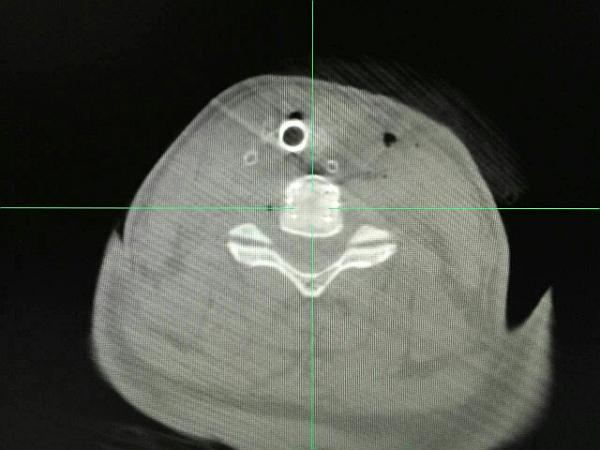

术前O-ARM定位颈5-6椎间盘节段

定位针再次确定颈5-6椎间盘位置并再次确定导航计划